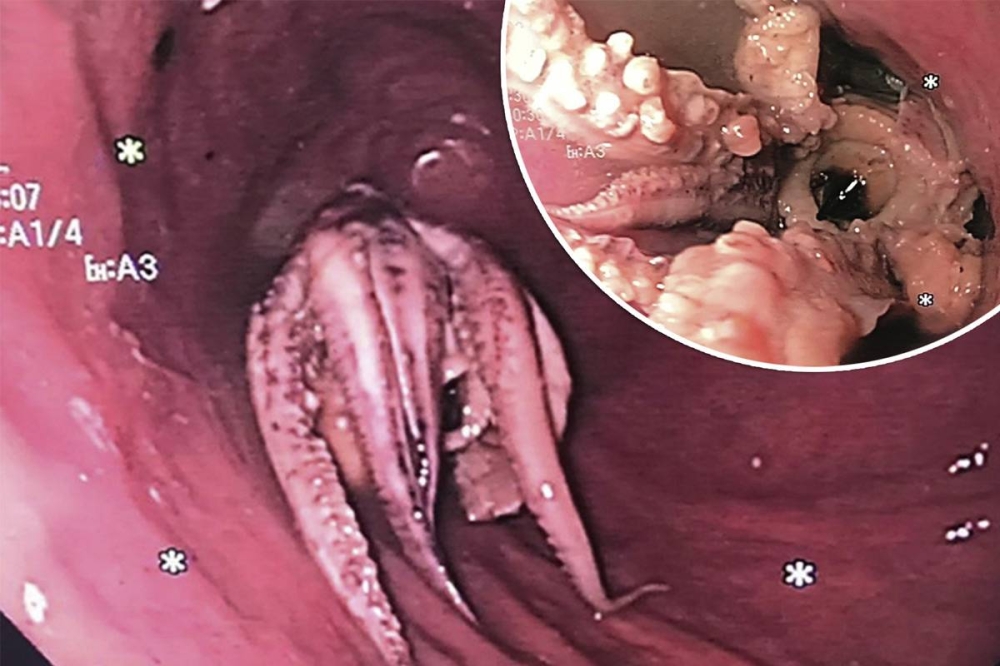

صُدم الأطباء في سنغافورة من اكتشاف أخطبوط استقر في مريء رجل أثناء إجراء فحص الجهاز الهضمي لمعرفة سبب القيء لديه.

وشارك معهد الجمعية الأميركية للجهاز الهضمي (AGA) صوراً مأخوذة من كاميرا المنظار الداخلي، تُظهر المخلوق ذي المجسات الثمانية العالق في مريء الرجل. في البداية، جرب الأطباء «تقنية الدفع» ولكن سرعان ما اتضح أن الأخطبوط لن ينزل للأسفل، والضغط المفرط قد يؤدي إلى تمزق المريء، ولذلك كان عليهم استخدام الملقط للإمساك بالمخلوق البحري وسحبه خارج المريء.